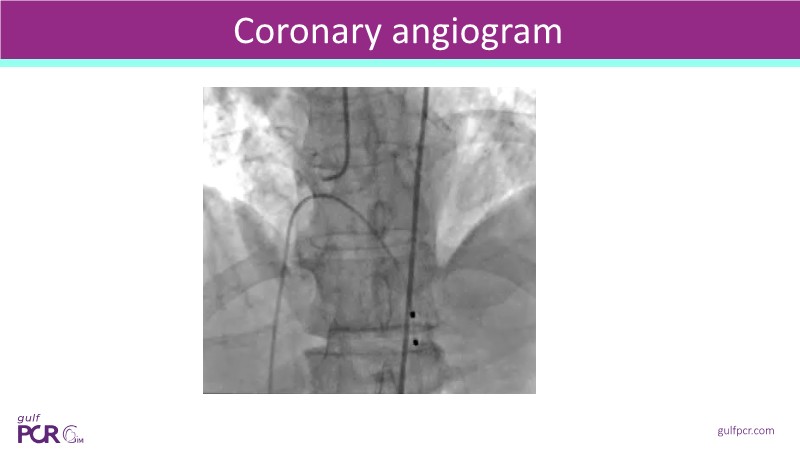

Calcified coronary lesions are a major challenge in PCI. This PCRGulf-GIM 2025 session showcases a complex case with intravascular imaging, highlighting how IVUS 123 guides each step.

From planning the procedure and understanding calcium distribution, to lesion preparation with modern modification tools, and post-PCI assessment to confirm stent expansion and detect complications, this session demonstrates practical, imaging-driven strategies.